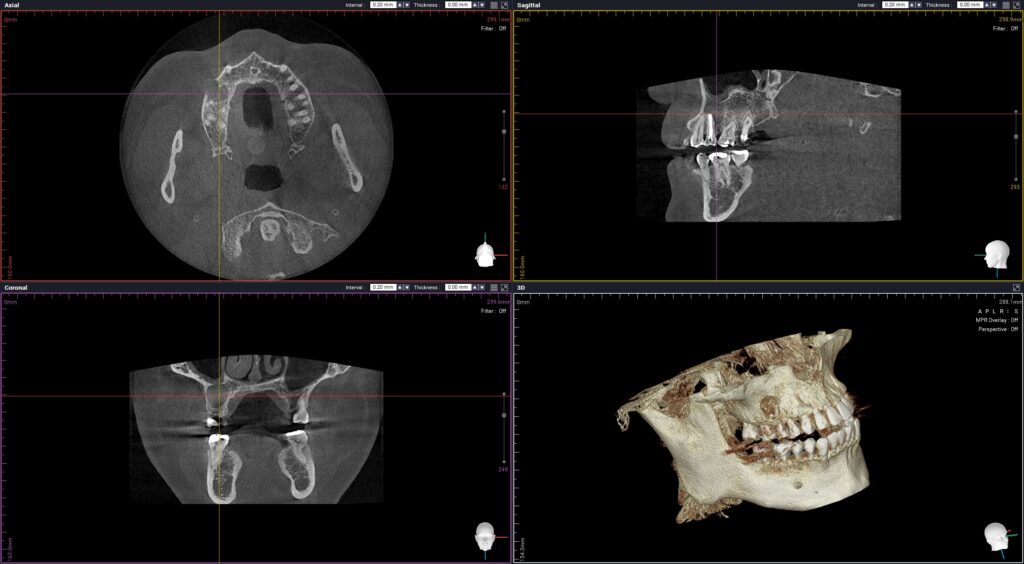

환자분께서는 신경치료 후 크라운을

진행하지 않았던 오른쪽 위 작은 어금니

뿌리의 큰 낭종이 생겨 있는 상태였는데요.

위턱뼈의 3개 치아가 넘는 크기의

낭종으로 제거가 필요한 상황임을

설명드리고 치료 계획을 수립하였습니다.

치근낭 또는 치근단 낭종은 말 그대로

치아 뿌리 쪽에 생긴 낭종을 의미하는데

턱뼈 내에 발생하는 가장 흔한 낭종입니다.

뿌리 끝으로 염증이 퍼지고 만성화되어

발생하며 심한 충치를 방치했거나

내부의 신경이 손상을 입어 괴사했을 때

쉽게 발생할 수 있습니다.

이는 초기에 증상이 없는 경우가 대부분이기 때문에

충치 등 다른 질환으로 검진을 받는 중 우연히

발견되는 경우가 많은 편인데요.